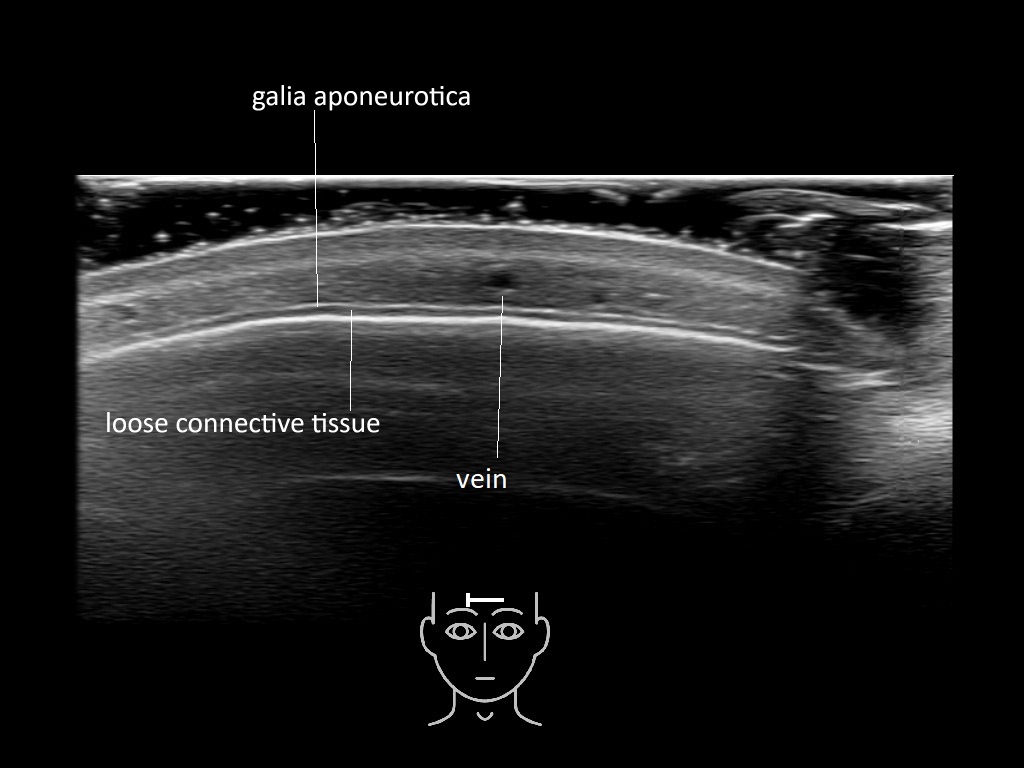

In this section you will learn more about the different layers of the face with the use of ultrasound. When you click on the secondary ultrasound image, you will see the different structures as an overlay. This will help to train yourself to recognize the different layers of the face.

Study the first image to recognize the different layers. If you are sure about the layers, swipe to the second image to view the answer (if applicable).